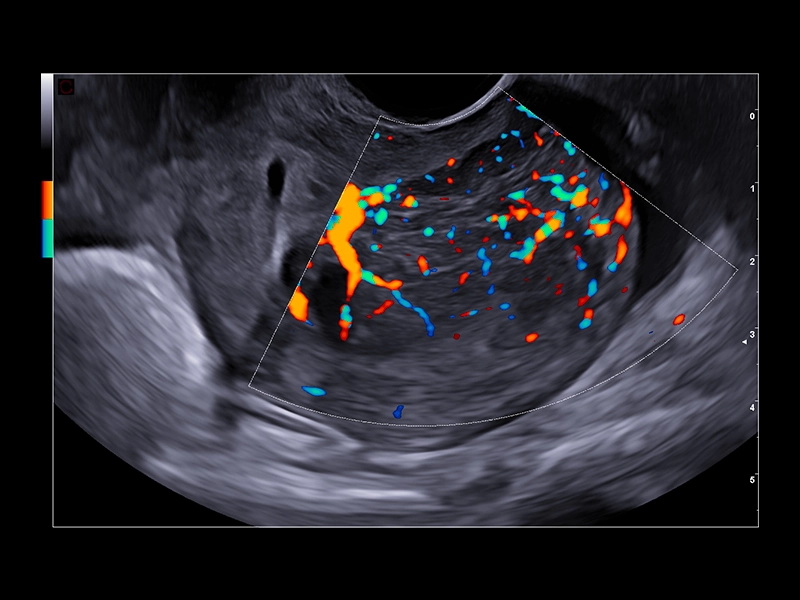

MyLab™E80 - Power Doppler - Gynaecology

MyLab™E80 - Power Doppler - Gynaecology